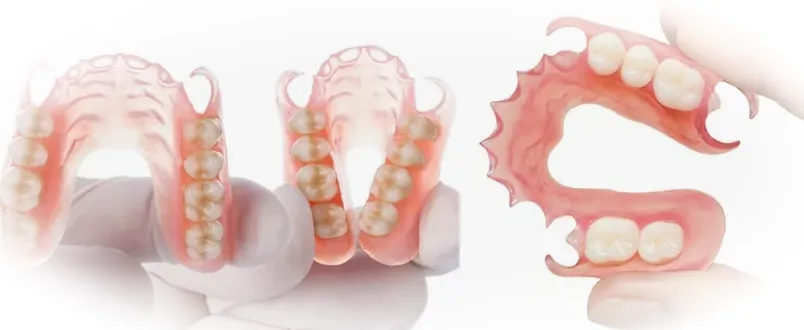

Силиконовые зубные протезы представляют собой съемные конструкции, изготовленные из специального мягкого материала, известного как эластомер. Этот материал обладает гибкостью и комфортностью, обеспечивая удобную посадку и снижая риск раздражения десен.

- Мягкий и гибкий материал обеспечивает удобство при ношении, уменьшая давление на десны.

- Приспосабливается к форме челюсти пациента, создавая индивидуальное ощущение комфорта.

- Цвет и прозрачность силикона позволяют протезу выглядеть естественно и незаметно.